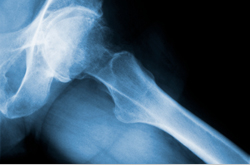

Artrose is een veelvoorkomende gewrichtsaandoening, vooral op hogere leeftijd. Zij komt vooral voor in knieën en heupen, en vaker bij vrouwen dan bij mannen. In de volksmond heet artrose een vorm van slijtage van het kraakbeen, maar dat wil niet zeggen dat er niets aan te doen is. Door voldoende lichaamsbeweging – ook bij pijn – kan het kraakbeen zelfs weer dikker en steviger worden. Angst voor pijn zet echter vaak een cirkel naar minder bewegen en meer pijn in gang. Het NIVEL (Nederlands instituut voor onderzoek van de gezondheidszorg) heeft een internetprogramma ontwikkeld om deze cirkel te doorbreken. Het helpt mensen met artrose meer en gedoseerd te bewegen. Bij de deelnemers worden de effecten van het beweegprogramma op de klachten en dagelijkse activiteiten gemeten. Blijkt het programma effectief, dan komt het beschikbaar voor iedereen met knie- en heupartrose.

Artrose In Beweging is ontwikkeld voor mensen tussen de 50 en 70 jaar die last hebben van artrose in heupen of knieën en die meer willen bewegen. Om te kunnen deelnemen aan het programma en het onderzoek mogen ze niet tegelijkertijd actief onder behandeling zijn bij een fysiotherapeut of specialist.